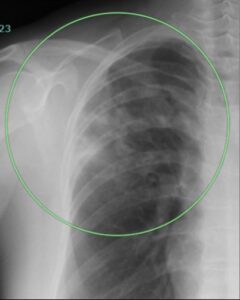

(実際の症例 乾酪性肺炎 51歳女性)

胸部X線

右肺上部に白い影がありますが、普通の肺炎と区別がつきません。